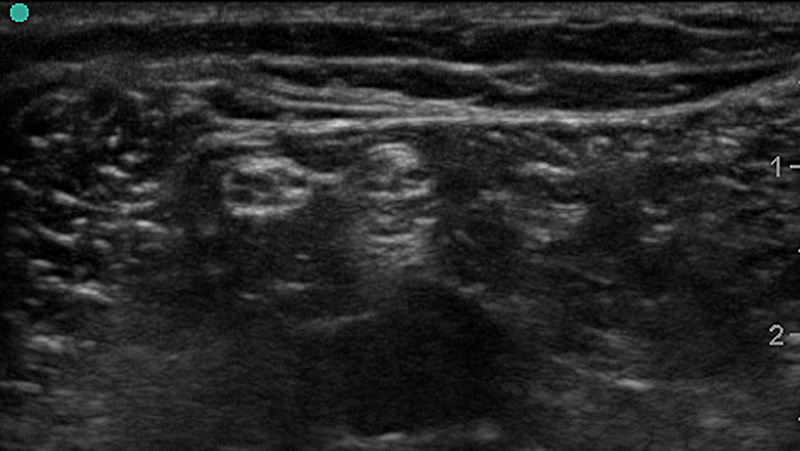

- Classically, nerves have a honeycomb-like appearance in cross section caused by bundling of hypoechoic nerve fascicles within hyperechoic peri- and endoneurium.

Figure 1a. Ultrasound Image of Peripheral Nerves

Figure 1b. Ultrasound Image of Peripheral Nerves With Labels